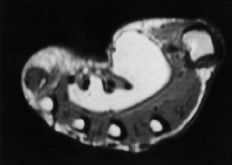

Lipomas

Fue la cuarta variedad histológica en frecuencia de la presente serie, con un total de 39 casos, de los cuales 26 afectaron a mujeres. La edad media de los pacientes fue de 55 ± 14 años (máximo: 74 y mínimo: 18 años), siendo el grupo de mayor edad. La localización típica de los lipomas fueron las eminencias y comisuras (21 casos), siendo los dedos la segunda más frecuente (11 casos); no hubo ningún caso localizado distal a las articulaciones IFP. La mayoría de los TPB de la mano localizados en las eminencias tenar e hipotenar y primera comisura fueron lipomas.

Los lipomas fueron los tumores de mayor tamaño de la serie, siendo el tamaño medio de 3,3 * 2,7 cm (máximo: 6,6 * 6 y mínimo: 0,7 * 0,5 cm). Dado el gran tamaño que pueden alcanzar en la palma, la afectación de varios radios fue frecuente. En las comisuras fue habitual que el crecimiento tumoral traspasara al compartimento dorsal. El tamaño de los lipomas ubicados en las eminencias fue en algunos casos muy considerable; un lipoma hipotenar llegó a pesar 95 gramos. A pesar de su gran tamaño, estos tumores eran indolentes, multilobulados, adaptándose en su crecimiento a las estructuras adyacentes. Independientemente de localizarse en zonas con pedículos vasculonerviosos como el canal de Guyon, no ocasionaron déficit sensitivomotores en ningún caso.

La RM fue típica, apareciendo imágenes homogéneas de aumento de intensidad de señal en T1 (Fig. 4). Los casos en los que se llevó a cabo RM con reconstrucción tridimensional ésta permitió ubicar el tumor en su entorno, facilitando su resección (Fig. 5).

Las características arriba mencionadas respecto de la localización, tamaño y dificultad de delimitación obligan a la realización de estudios de RM, que demuestran un patrón típico de aumento de señal homogéneo en las secuencias potenciadas en T1 (Fig. 4).10,17,29 Dados los resultados y la utilidad de la RM en muchos de los casos de esta serie, su realización se recomienda sobremanera.

Figura 4. Lipoma hipotenar. Corte transversal de RM potenciada en T1 en la que se aprecia la relación de la tumoración con las estructuras vasculonerviosas y tendinosas palmares, así como digitaciones intermetacarpianas.